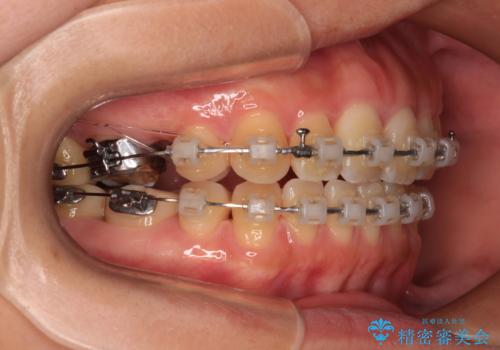

- 矯正装置

- クリアブラケット

- 1年10ヶ月

- 治療回数

- 10-30回

上顎左右の小臼歯2本および下顎小臼歯を1本抜歯し、補助装置を用いて上顎大臼歯が前方に移動しないように固定した上で、ワイヤー装置にて矯正治療を行うこととしました。

上下前歯のズレは舌の突出癖による影響も大きいと考えられたたため、舌のトレーニングをしっかりと行っていただきました。